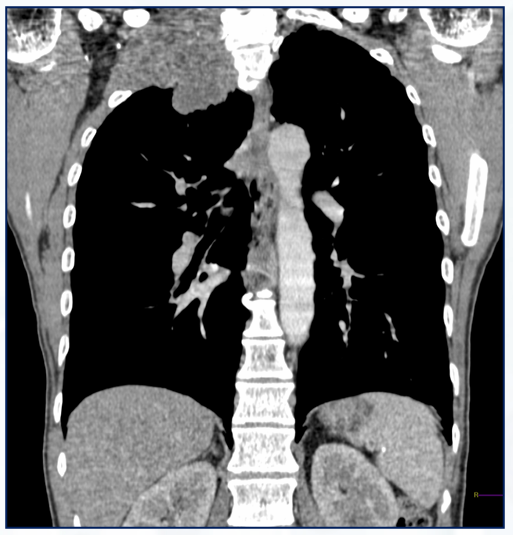

Qual o achado dessa TC de tórax axial?

Destruição e desorganização do parênquima pulmonar, determinando focos de aprisionamento aéreo e redução da atenuação pulmonar (pulmão mais preto).

Enfisema pulmonar

Mais comum nos ápices e segmentos superiores dos pulmões.